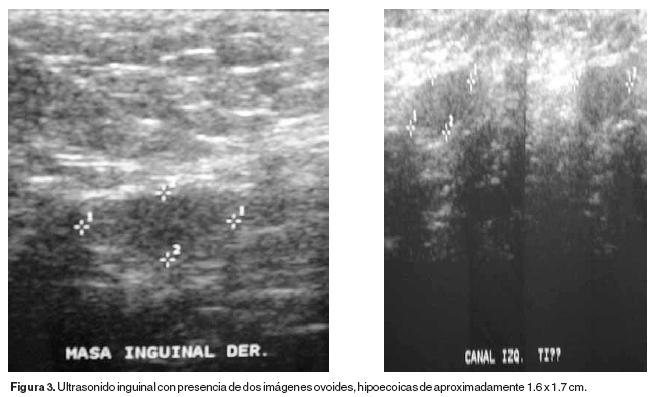

El ultrasonido inguinal confirmó ausencia de testículos en bolsas escrotales y en regiones inguinales presencia de imagen ovoide hipoecoica de 1.6 x 1.7cm (Figura 3). En la densitometría ósea se detectó osteoporosis.